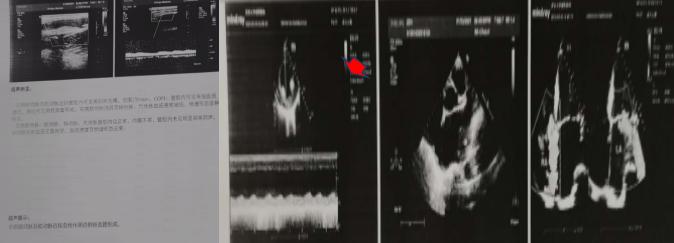

2021年1月20日心血管內科二病區接診一位56歲男性患者,以“右上肢疲乏無力“之主訴入院,患者右側橈動脈搏動消失、血壓無法測出。此患者發生了什么?患者基礎病為1.冠心病 急性非ST段抬高型心肌梗死 心房顫動2.腦梗死,為什么右橈動脈搏動消失、血壓無法測出?迅速聯系超聲室王英莉副主任和賈貝醫生,迅速對患者右上肢動脈、心臟超聲進行檢查,結果示:左心房內附壁血栓,其表面血栓動度明顯,存在再次脫落風險,上肢動脈后提示閉塞伴側枝血管形成。心血管內科二病區主任左梅教授再次對患者進行診查,建議立即啟動溶栓治療。經過連續5天的治療,患者的右橈動脈可觸及,血壓126/74mmHg。那么患者為什么會發生栓塞?栓子從哪里來?

其次危害:血栓栓塞。房顫時心房失去收縮功能,血流瘀滯在心房中,就容易結成血凝塊,就好像流速緩慢的河段有嚴重的泥沙淤積一樣。一旦血凝塊形成,又被血流沖刷脫落,血栓脫落后可隨著血流跑到全身各處,堵住血管,導致腦栓塞(中風)、內臟栓塞、肢體動脈栓塞等。非瓣膜病房顫患者發生中風的概率是普通人的5.6倍,而心臟瓣膜病合并的房顫則是17.6倍。